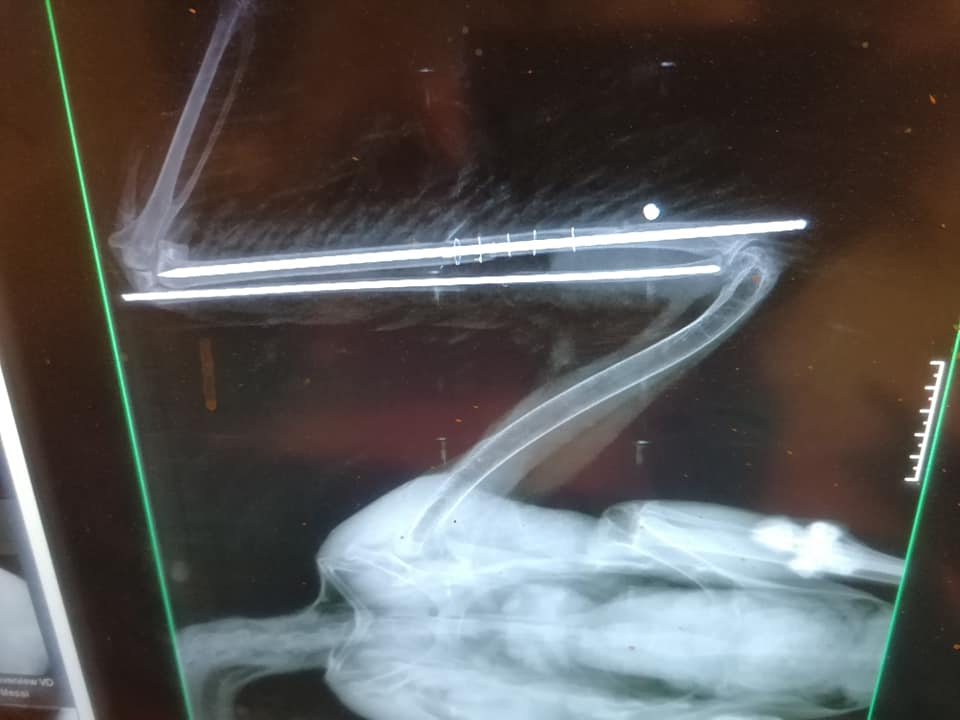

Mint írják, szerdán majdnem egyszerre szállítottak be egy légpuskával meglőtt fehér gólyát (fokozottan védett faj, eszmei értéke 100 ezer forint) és egy szabálytalanul kihelyezett csapóvas által fogott barna rétihéját (védett, eszmei értéke 50 ezer forint). Előbbi valószínűleg fészkel, tojásai jelenleg árván maradtak. A lövedék a madár felkarcsontját roncsolta, gyógyulása több mint 2 hónapig is eltarthat. Utóbbinak a csapóvas majdnem letörte a lábfejét, az állat jelenleg is válságos állapotban van.

Kép forrása.